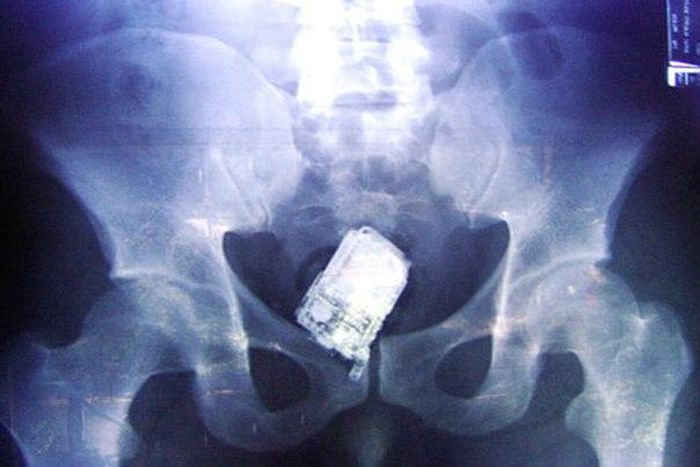

Phone 'left' inside woman after cesarean section

A mother who delivered her son by cesarean section says she was left with a mobile phone inside her body when she was sewn back up.

Hanan Mahmoud Abdul Karim, 36, underwent a cesarean section at a private hospital in Jordan giving birth to a baby boy weighing 10lbs 8ozs.

However, after the new mother experienced abdominal vibrations, her family rushed her to the public Al Bashir hospital where doctors allegedly found the foreign object and removed the phone.